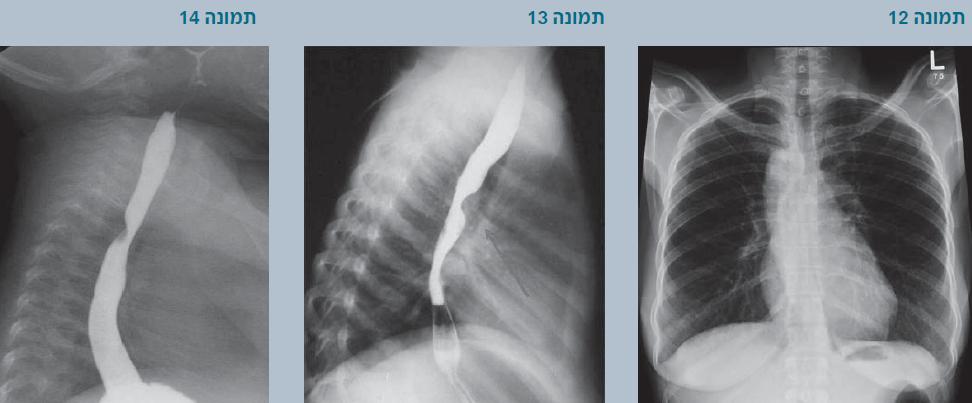

צילום חזה

בצילום חזה חשוב לנסות לראות אם יש קשת אבי-עורקים ימנית. קיום קשת ימנית מכוון אותנו לחשוב על אפשרות של טבעת וסקולרית. עוזר אם משלבים את הצילום גם עם בליעת בריום.

- בתמונה 11: רואים שקע (אינדנטציה) על הקנה משמאל, מתאים לקשת אבי-עורקים שמאלית.

- בתמונה 12: רואים שקע על הקנה מצד ימין שמחשיד מאוד לקשת ימנית.

- בתמונה 13: נראה לחץ מלפנים על הוושט, ואולי גם אחורי על הקנה, מתאים ללולאה וסקולרית, כאשר עורק הריאה השמאלי האנומלי עובר בין הקנה לוושט.

- בתמונה 14: נראה לחץ אחורי אלכסוני על הוושט שאופייני לעורק תת-בריחי ימני אנומלי (Anomalous right subclavia) שיוצא אחרון מקשת שמאלית ועובר ימינה מאחורי הוושט.

- תמונה 15: לחץ דו-צדדי על הוושט כאשר השקע מימין (של הקשת הימנית) גבוה יותר. מתאים לקשת אבי-עורקים כפולה. בתמונה מימין נראית תמונת אנגיוגרפיה של קשת אבי-עורקים כפולה.